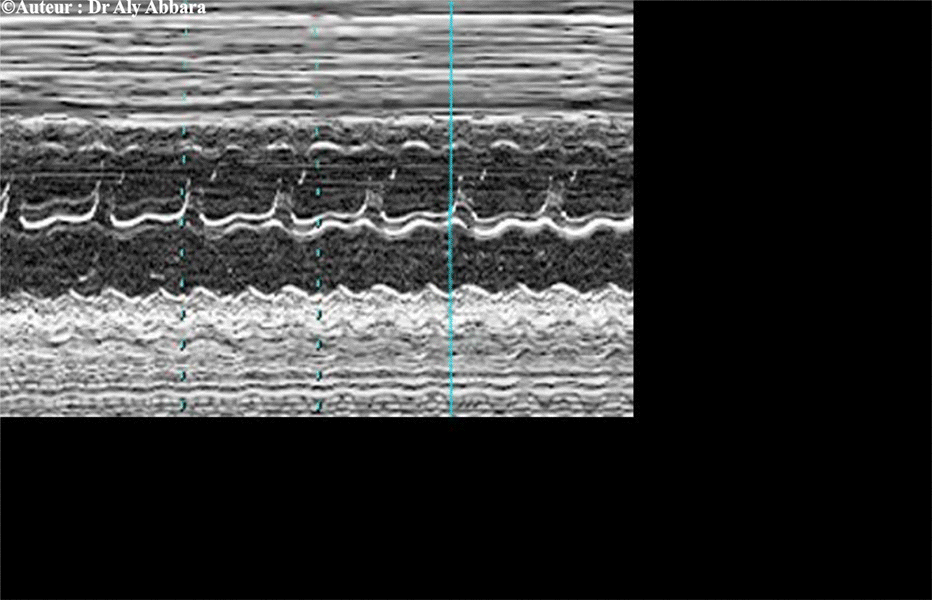

Mode-M

Flutter auriculo-ventriculaire

Analyse du spectre mod-M

Flutter auriculo-ventriculaire - détails

• Chez le fœtus, le flutter auriculaire se caractérise par une fréquence auriculaire supérieure à la fréquence ventriculaire.

• La fréquence auriculaire varie de 300 à 600 bpm ; elle est régulière.

• Le bloc auriculo-ventriculaire est variable :

• Quand il s'agit d'un bloc auriculaire de type "2:1", la fréquence ventriculaire est régulier et égale à la moitié de la fréquence auriculaire.

• Quand il s'agit d'un bloc auriculo-ventriculaire variable, il résulte une fréquence ventriculaire irrégulière de l'ordre de 150 à 250 bpm et un bloc auriculo-ventriculaire allant de 2:1 à 4:1.